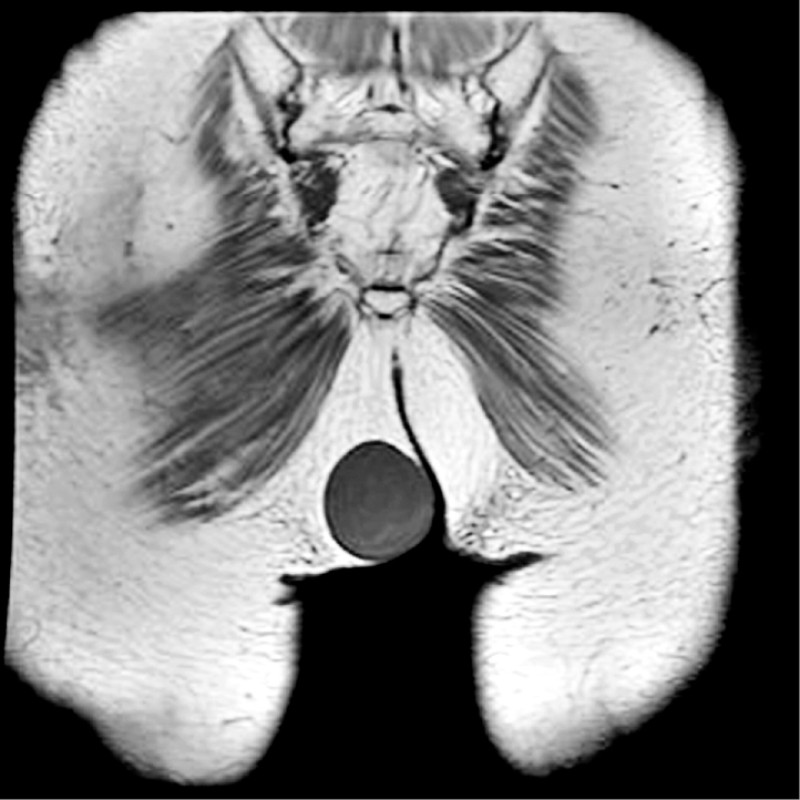

經安排核磁共振檢查,顯示腫瘤體積約48×57×54毫米,幾乎是1顆桃子般大小,屬於相當大型的粉瘤,雖然是良性腫瘤,但只要受到撞擊、感染或反覆壓迫,就可能在短時間內紅腫化膿,甚至像「皮下火山」般劇痛,嚴重時可能因細菌擴散引發蜂窩性組織炎,甚至敗血症,因此建議手術治療。